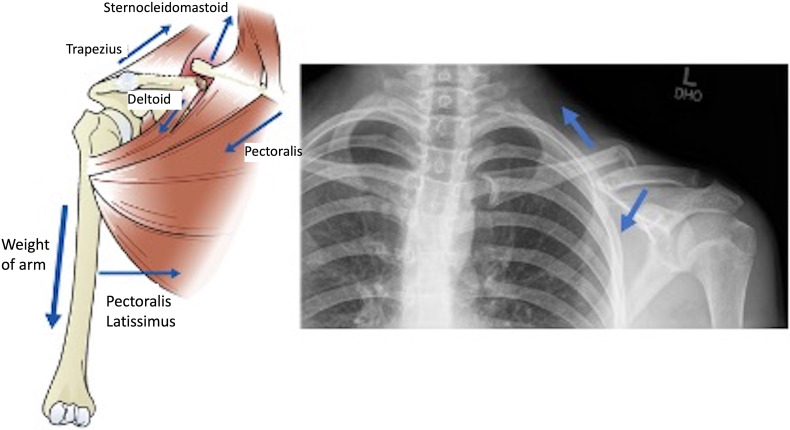

本综述的目的是描述儿童和青少年患者锁骨中轴骨折移位的处理方法。锁骨中轴骨折在儿童和青少年患者中相对常见。它们最常由直接创伤引起,通常与青少年参加体育运动有关。最近关于成人锁骨中轴骨折治疗的文献支持手术治疗,因为手术治疗改善了功能预后,缩短了愈合时间,可以早期恢复活动。在儿科和青少年患者中也出现了类似的手术治疗频率增加的趋势,但关于最佳治疗的文献没有达成共识。非手术治疗包括短时间的吊带固定,随后活动范围。开放性骨折、有明显神经血管损伤和软组织并发症的骨折可考虑手术治疗。研究显示小儿锁骨中轴骨折手术和非手术治疗后的中长期功能和患者报告的结果相当。

The purpose of the current review is to describe the management of displaced midshaft clavicle fractures in pediatric and adolescent patients. Midshaft clavicle fractures are relatively common in pediatric and adolescent patients. They most commonly occur from direct trauma and are often related to sports participation in adolescents. Recent literature in the management of adult midshaft clavicle fractures has supported operative management due to improved functional outcomes, decreased time to union, leading to early return to activity. A similar trend of increasing frequency in operative management has been seen in pediatric and adolescent patients with no consensus in the literature on optimal management. Nonoperative treatment consists of with a brief period of sling immobilization followed by range of motion. Operative management may be considered for open fractures, fractures with significant neurovascular compromise and soft tissue complications. Studies have shown comparable mid- to long-term functional and patient-reported outcomes after operative and nonoperative management of midshaft clavicle fractures in pediatric patients.